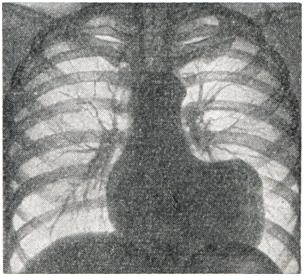

Рис. 4.

Аневризма левого желудочка. Увеличение поперечника сердца влево. Прямоугольные очертания левого контура сердца (рентгенограмма)..